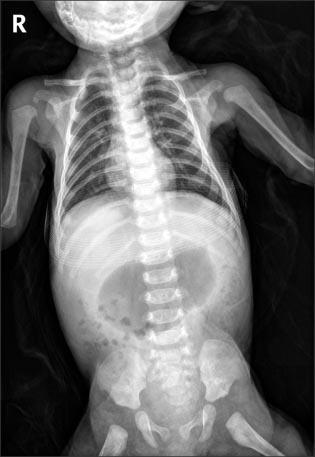

Abdominal X-ray showed marked gastric distension (

Fig. 1), and abdominal US revealed hypertrophied pyloric canal with 2.5 cm of length and 0.6 cm of thickness (

Fig. 1The infantogram shows distended stomach.